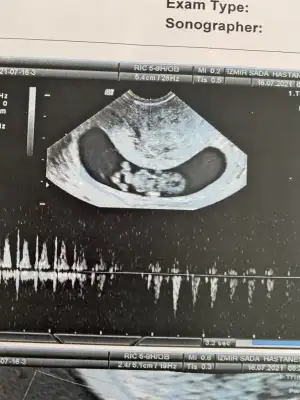

En iyi 11 12 13 haftalar olmalıIkra meyra merhaba 9+5 bugün çekildik bi tahminin var mı cnm ?

Erkek gibiBuda benim yorumlayabilirmisin![]()

Belkide erkektir ben USG göre tahmin ediliyorum Dr gibi detaylı bakmıyorum kaç haftalık ta tahmin etti DrDoktor üçtür erkeğe benziyor ama net değil diyor demekki kız![]()